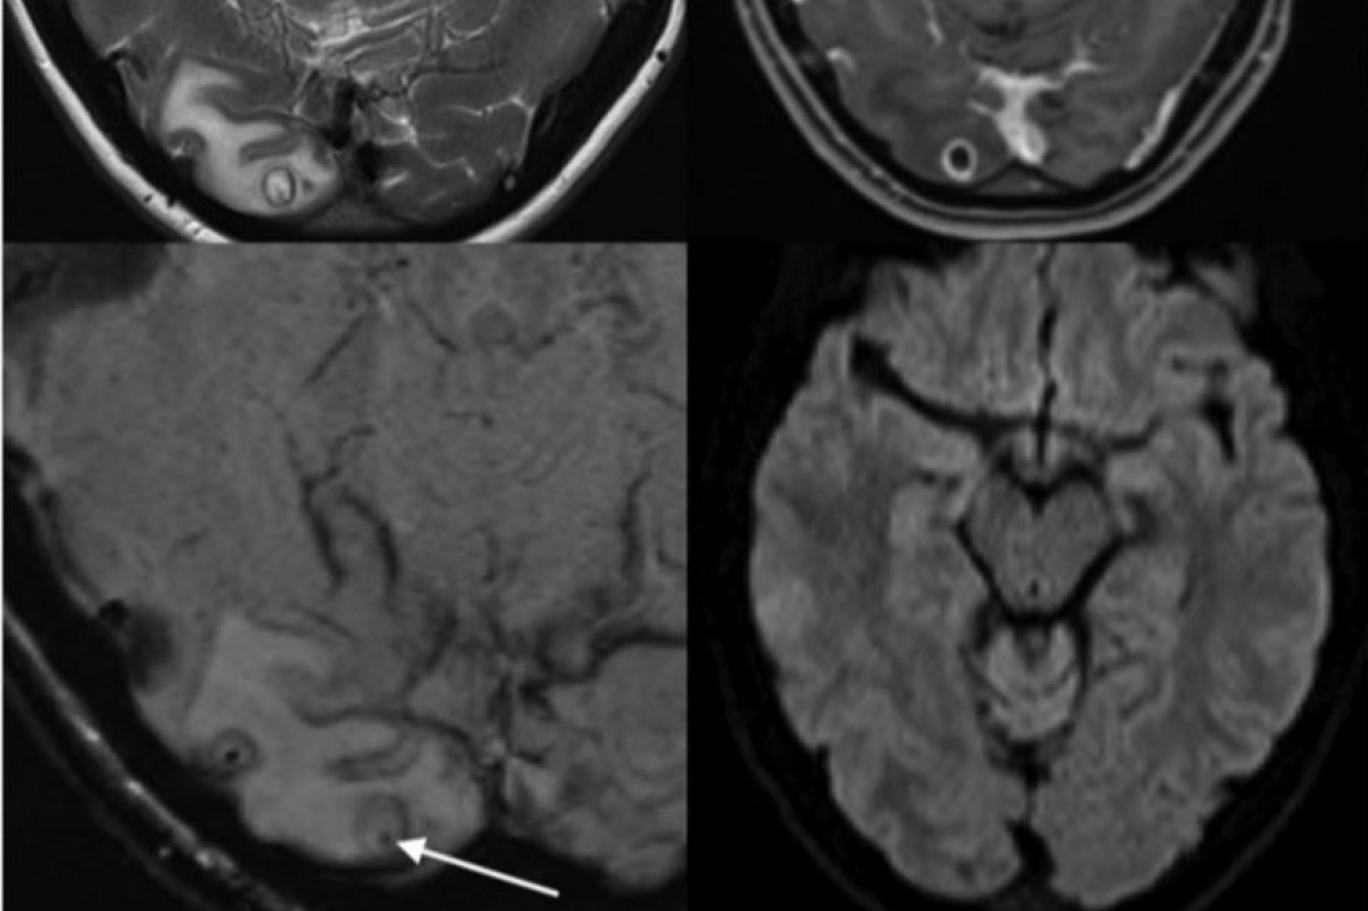

Mirror’ın haberine göre; Doktorlar, şiddetli baş ağrıları yaşayan kadının beyninde büyüyen bir tenya larvası buldular.

Yadira Rost, şiddetli baş ağrılarıyla 9 ay önce tanıştı. Ve iyice şiddetlenen ve daha da kötüleşen bu ağrılar nedeniyle tıbbi yardım almaya karar verdi.Beyninde kurt larvası olduğu belirlenen kadın ameliyata alındı. 31 yaşındaki kadın şimdi 2 yıl önce yaptığı Meksika gezisinde hastalık kaptığına inanıyor.